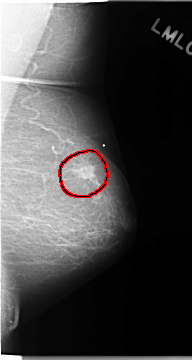

C_0118_1.RIGHT_MLO

LEFT_MLO LINES 4672 PIXELS_PER_LINE 2488 BITS_PER_PIXEL 12 RESOLUTION 50 OVERLAY

FILE: C_0118_1.LEFT_MLO.OVERLAY

TOTAL_ABNORMALITIES 1

ABNORMALITY 1

LESION_TYPE MASS SHAPE IRREGULAR MARGINS ILL_DEFINED

ASSESSMENT 5

SUBTLETY 5

PATHOLOGY MALIGNANT

TOTAL_OUTLINES 1

BOUNDARY